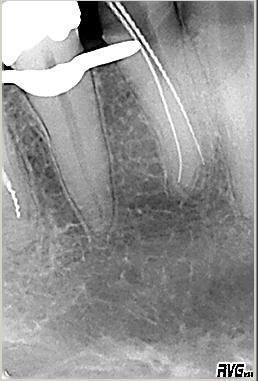

Röntgenmessaufnahme

Röntgenmessaufnahme nach vorgängig durchgeführter endometrischer Längenbestimmung